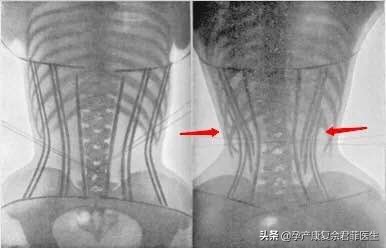

3、 骨头 、韧带变形:当束腰所产生的压力过大,会让骨头和韧带发生变形。而如果骨头和器官的结构发生改变,对脊柱来说,造成的影响是不可逆转的。

6、 脏器脱垂:长时间佩戴束腰,而脂肪没有减少、肌肉也没变,但腰变细了,很大原因说明,内脏受到了严重挤压。当内脏的横向空间被挤压,但是体积不变,就会向上向下移位。容易引起盆腔脏器脱垂,严重者会有漏尿的情况,需要介入盆底康复治疗,严重者甚至需要手术治疗。